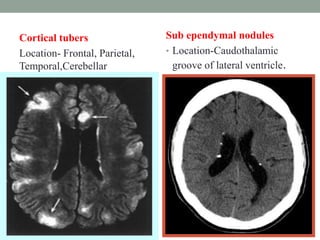

Cortical tubers

Location- Frontal, Parietal,

Temporal,Cerebellar

Sub ependymal nodules

• Location-Caudothalamic

groove of lateral ventricle.